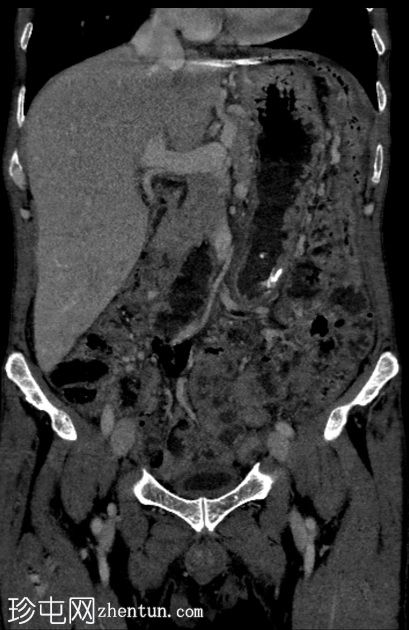

轴位增强扫描

门静脉期

盲肠内壁可见多条明显的血管通道,并可见局灶性强化。

动脉期可见一条早期充盈的静脉。静脉期可更清晰地显示扩张的引流静脉。未见活动性出血。